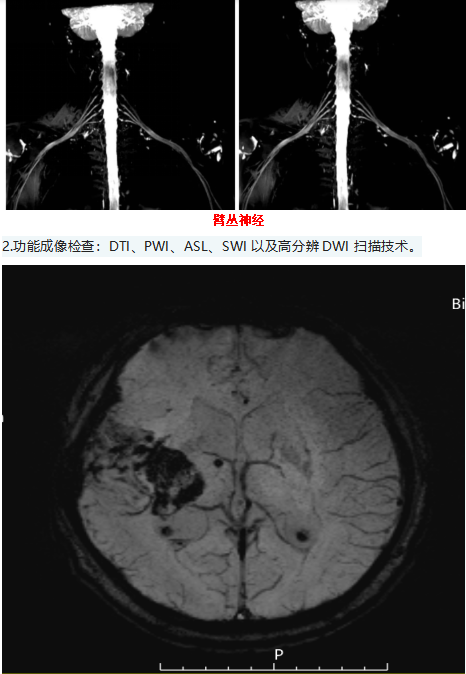

经过多年的磨合与探索,我们已经能够开展多种先进的检查,也能更好地满足医院医疗、教学、科研工作的需要。